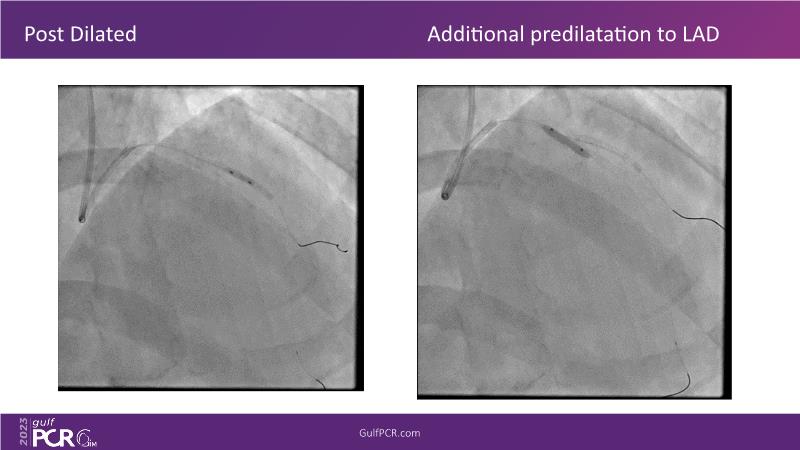

- To learn about the novel Myval next generation THV technology, its key features, procedural and clinical benefits and learn about the clinical data in a vast cohort of patient population

- To understand the technique of precise sizing, positioning and deployment of Myval THV